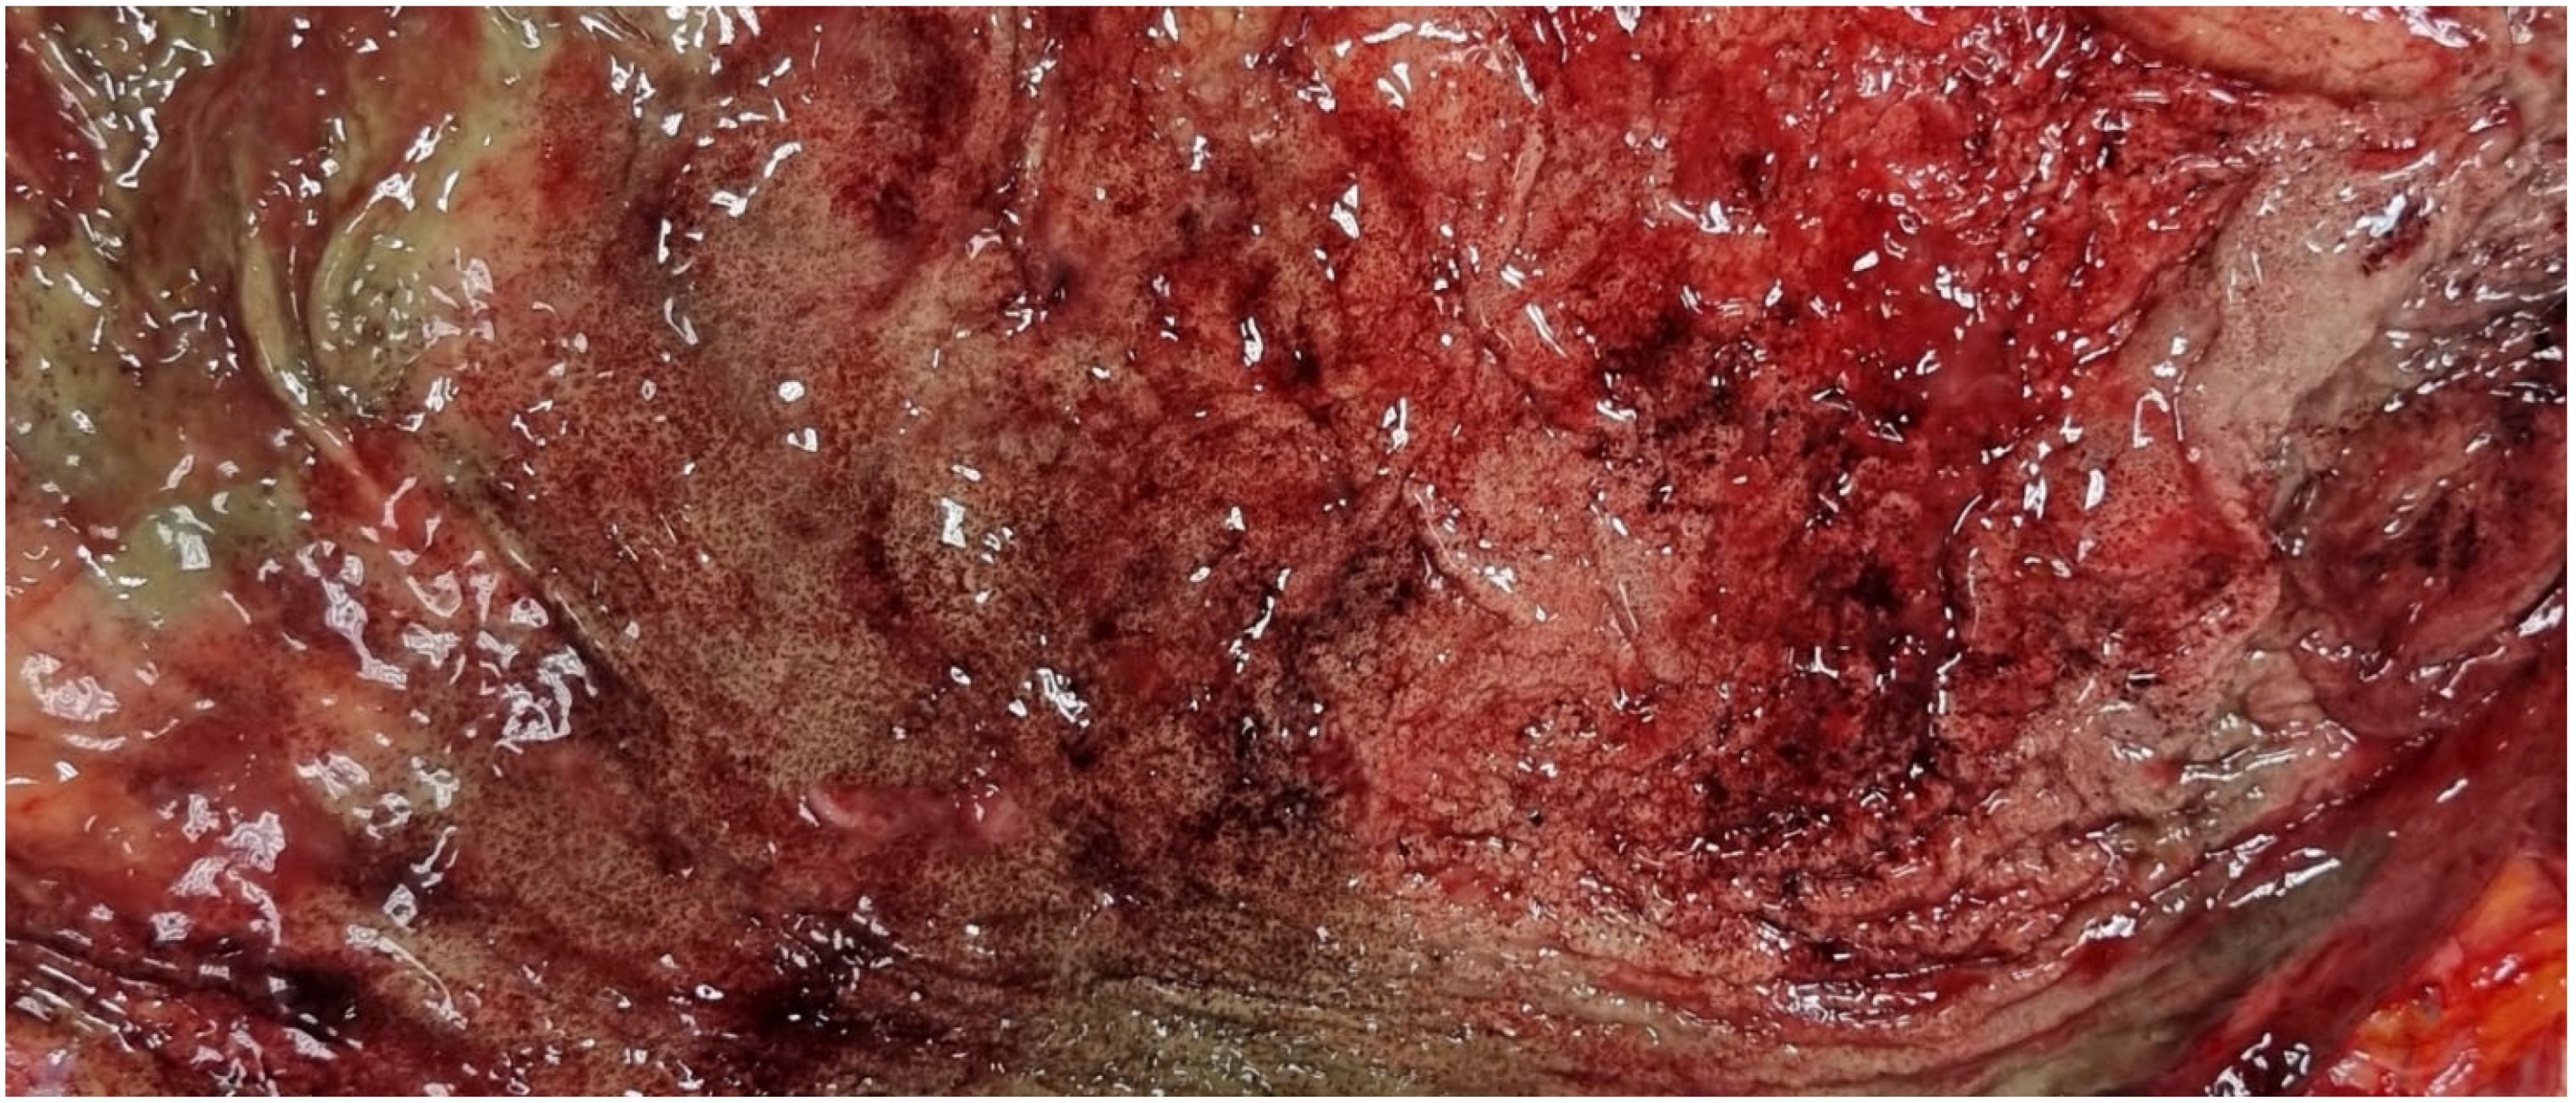

The body exhibited signs of partial rigor mortis and freezing. External examination revealed a median sternotomy scar consistent with a prior cardiac surgical procedure, along with postmortem lesions consistent with scavenging activity by wild animals. There was evidence of coronary artery bypass grafting, with complete patency of the graft between the aorta and the right coronary artery; the accessible coronary segments showed no significant atherosclerotic changes. Additionally, there were long and numerous red-brown streaks in various parts of the body, with a higher concentration in the gluteal region. Internal examination revealed good preservation of organs, remnants of double coronary artery bypass, mild chronic pulmonary emphysema, and modest steatotic hepatomegaly. Cerebral perivascular hemorrhages, superficial hemorrhagic erosions of the gastric mucosa (WSs) (Figure 4), and cerebral and pulmonary edema were also observed. Toxicological investigations yielded negative results.

Figure 4.

Case 2: Wischnewski spots represent a well-established indication of hypothermia in postmortem examinations, yet their occurrence in living individuals is exceedingly rare. The pathogenesis has been linked to disruptions in microcirculation, ischemic events, and reperfusion injuries [13].